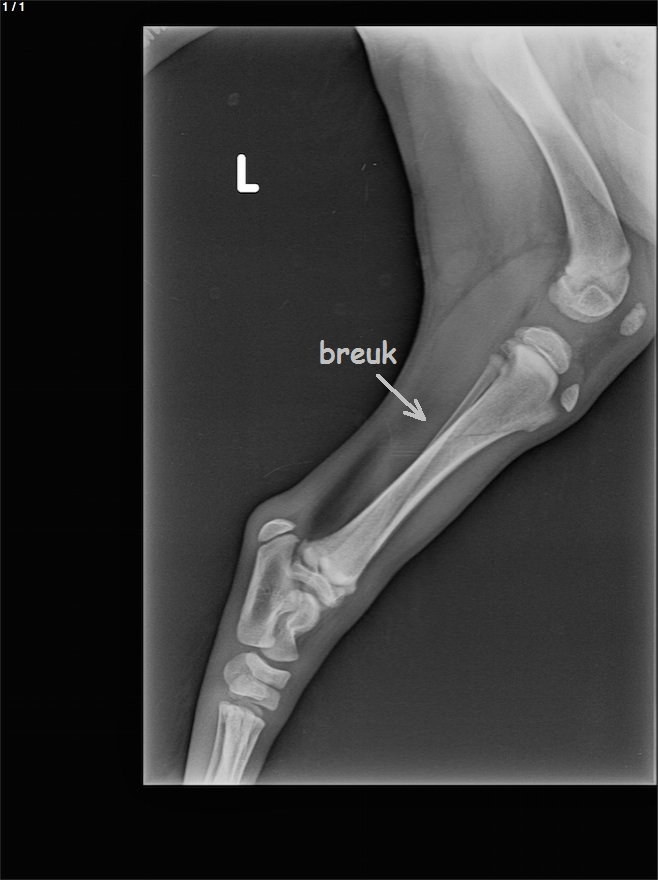

Een ongelukkig begin.

Binnen een week pootje gebroken door een te woeste actie van Buck.